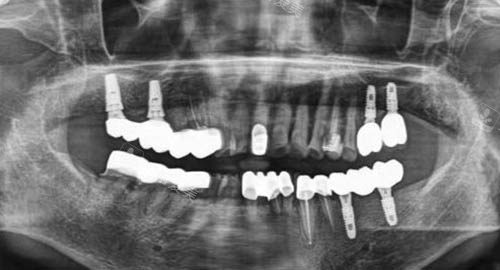

在诊断方面,它引进了靠前的口腔检查设备,如智能化口腔全景机、口腔内窥镜等,能够比较准地检测出患者口腔的各种问题,为后续的治疗提供更准的依据。

例如,对于牙齿缺失患者,提供多种种植牙方案供选择,包括不同品牌的种植体,以满足不同患者的经济和功能需求;对于牙齿矫正,采用靠前的隐形矫正技术,既美观又舒适。